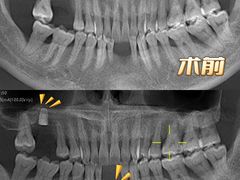

• Dr.Z dental仁康种植矫正中心

• -Dr.Z dental仁康种植矫正中心

糊涂印象 | 23-01-10